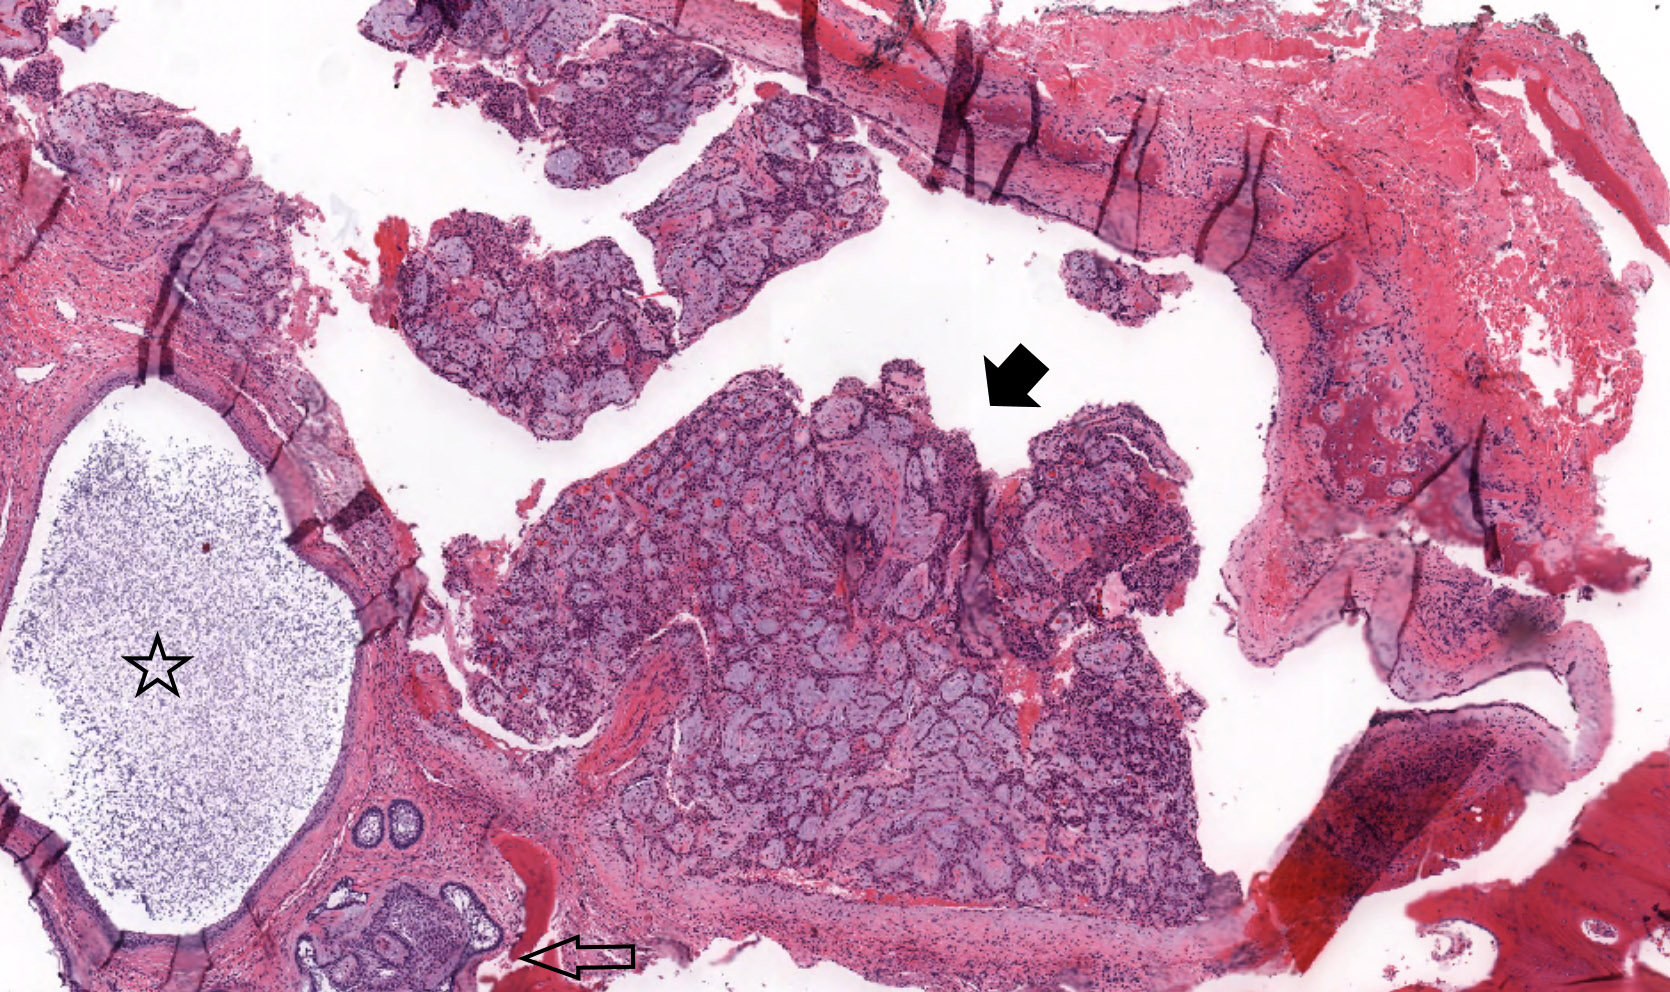

Microscopic (histologic) description

- Ameloblastoma, unicystic type has 3 histopathological patterns

- Single cystic lesion lined by ameloblastic epithelium that shows typical features of ameloblastoma in some areas, including columnar basal cells in palisading arrangement with vacuolated cytoplasm, hyperchromatic nuclei polarized away from basement membrane

- Suprabasal cells loosely textured and noncohesive resembling stellate reticulum, epithelial invagination, epithelial edema and separation

- Microscopic variants (may result in treatment differences - controversial)

- Luminal: cystic odontgenic epithelium with characteristic features (above) lining fibrous connective tissue wall

- Intraluminal: cystic odontgenic epithelium with characteristic features (above) lining fibrous connective tissue wall, with tumor extending into the cystic luminal space; may have intraluminal plexiform patterns

- Mural: cystic odontgenic epithelium with characteristic features (above) lining fibrous connective tissue wall but with the additional finding of definite ameloblastoma tumor islands within the fibrous connective tissue wall

Microscopic (histologic) images

Contributed by Kelly Magliocca, D.D.S., M.P.H. and Anne C. McLean-Holden, D.M.D., M.S.